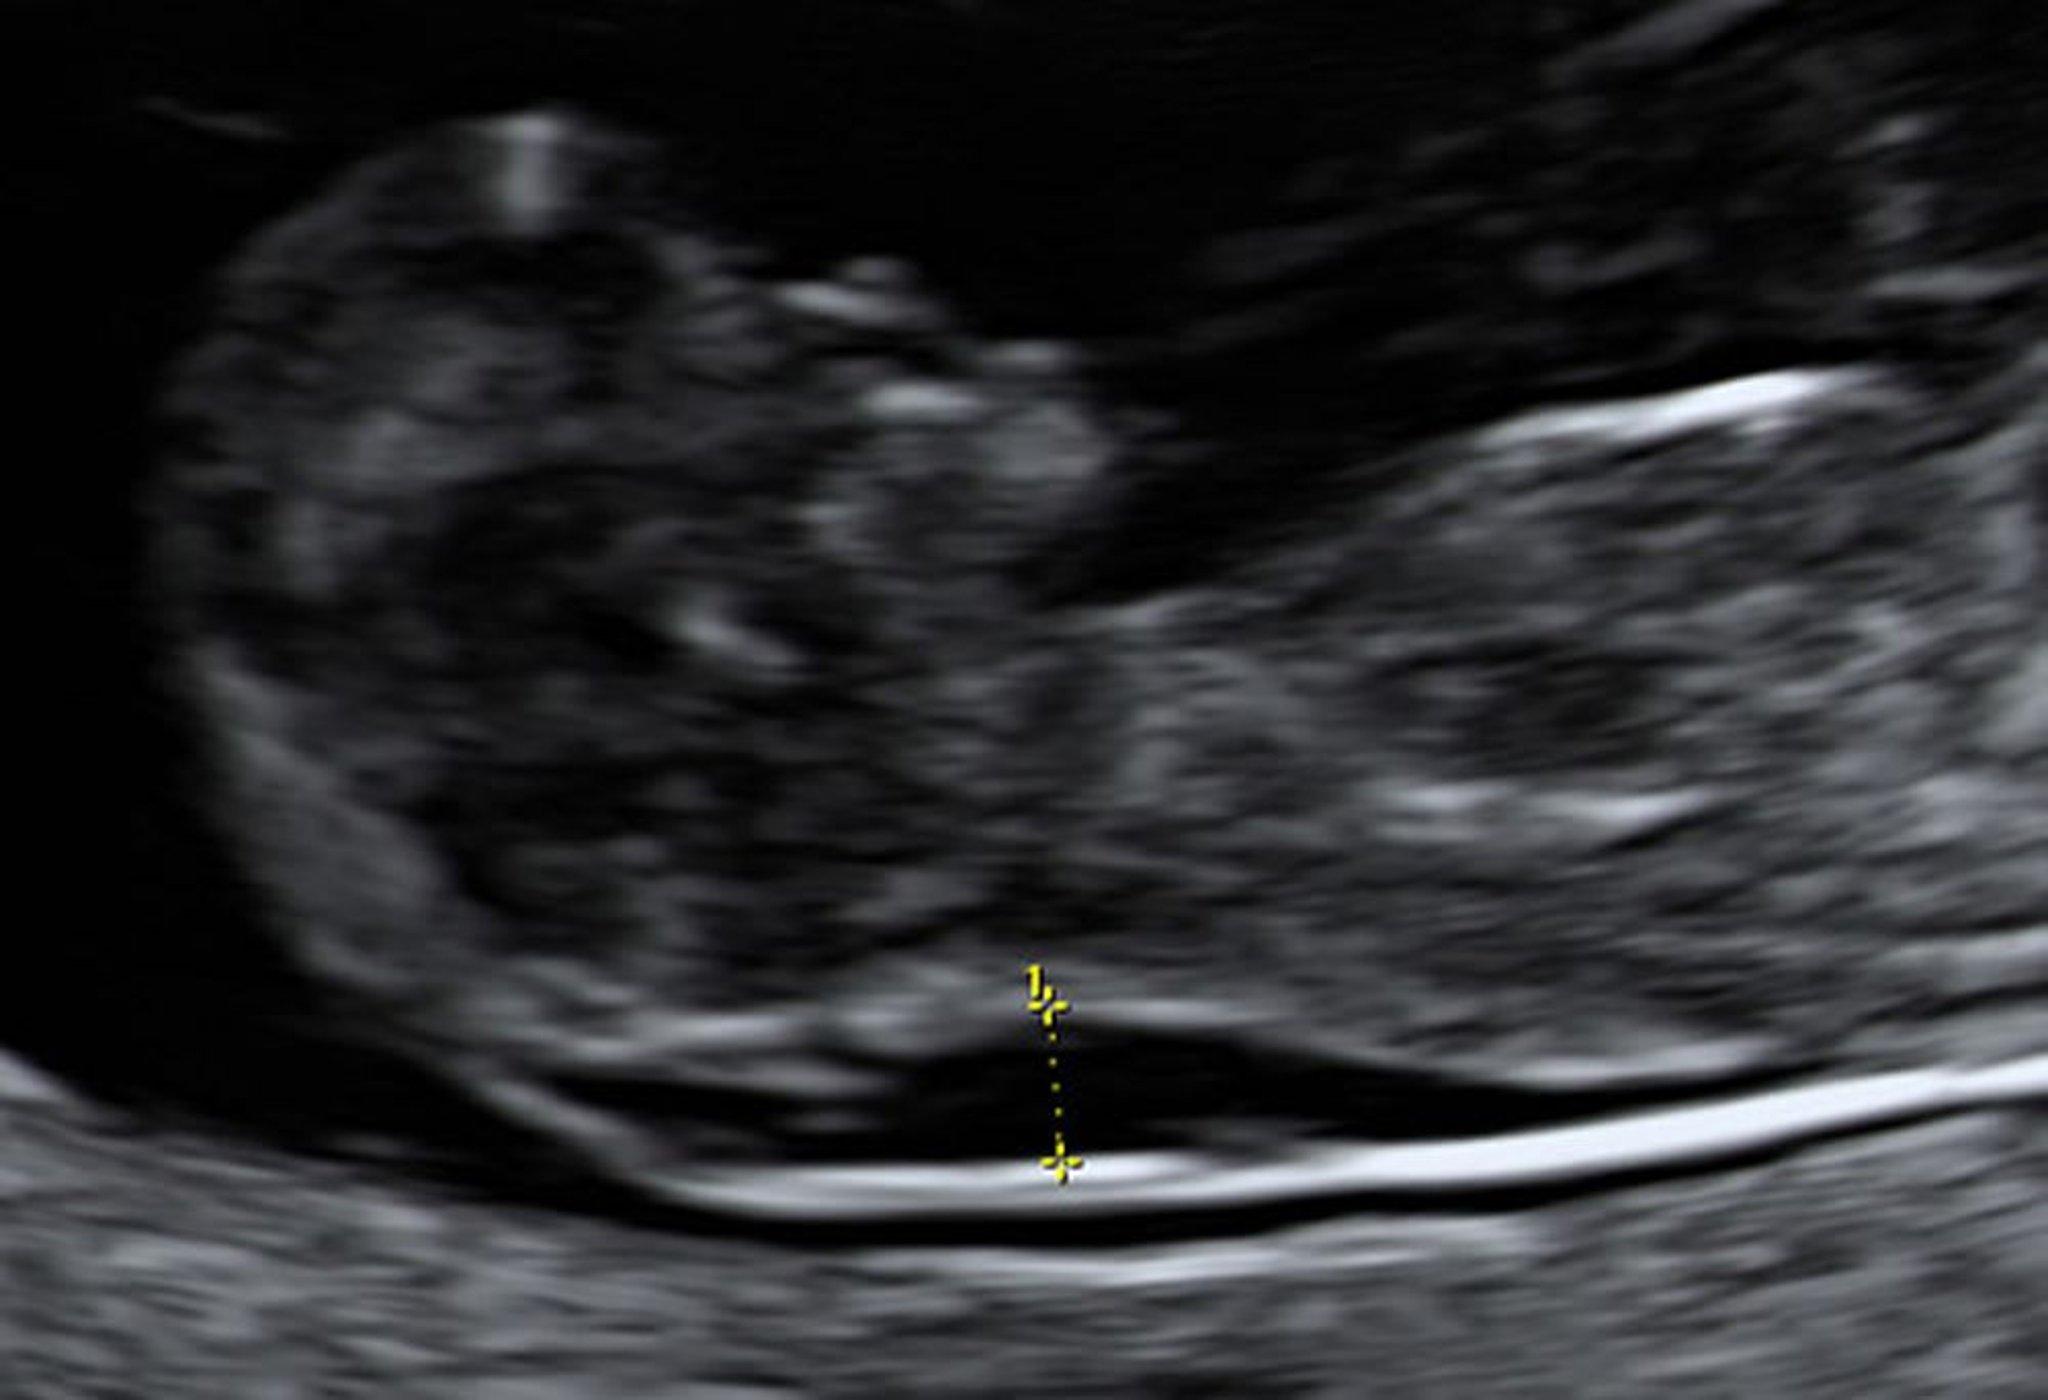

Ultrasonography Showing Enlarged Nuchal Translucency in a Fetus at 10 Weeks

Chorionic villus sampling indicated that this fetus had Down syndrome.

Photo from Jeffrey S. Dungan, MD.